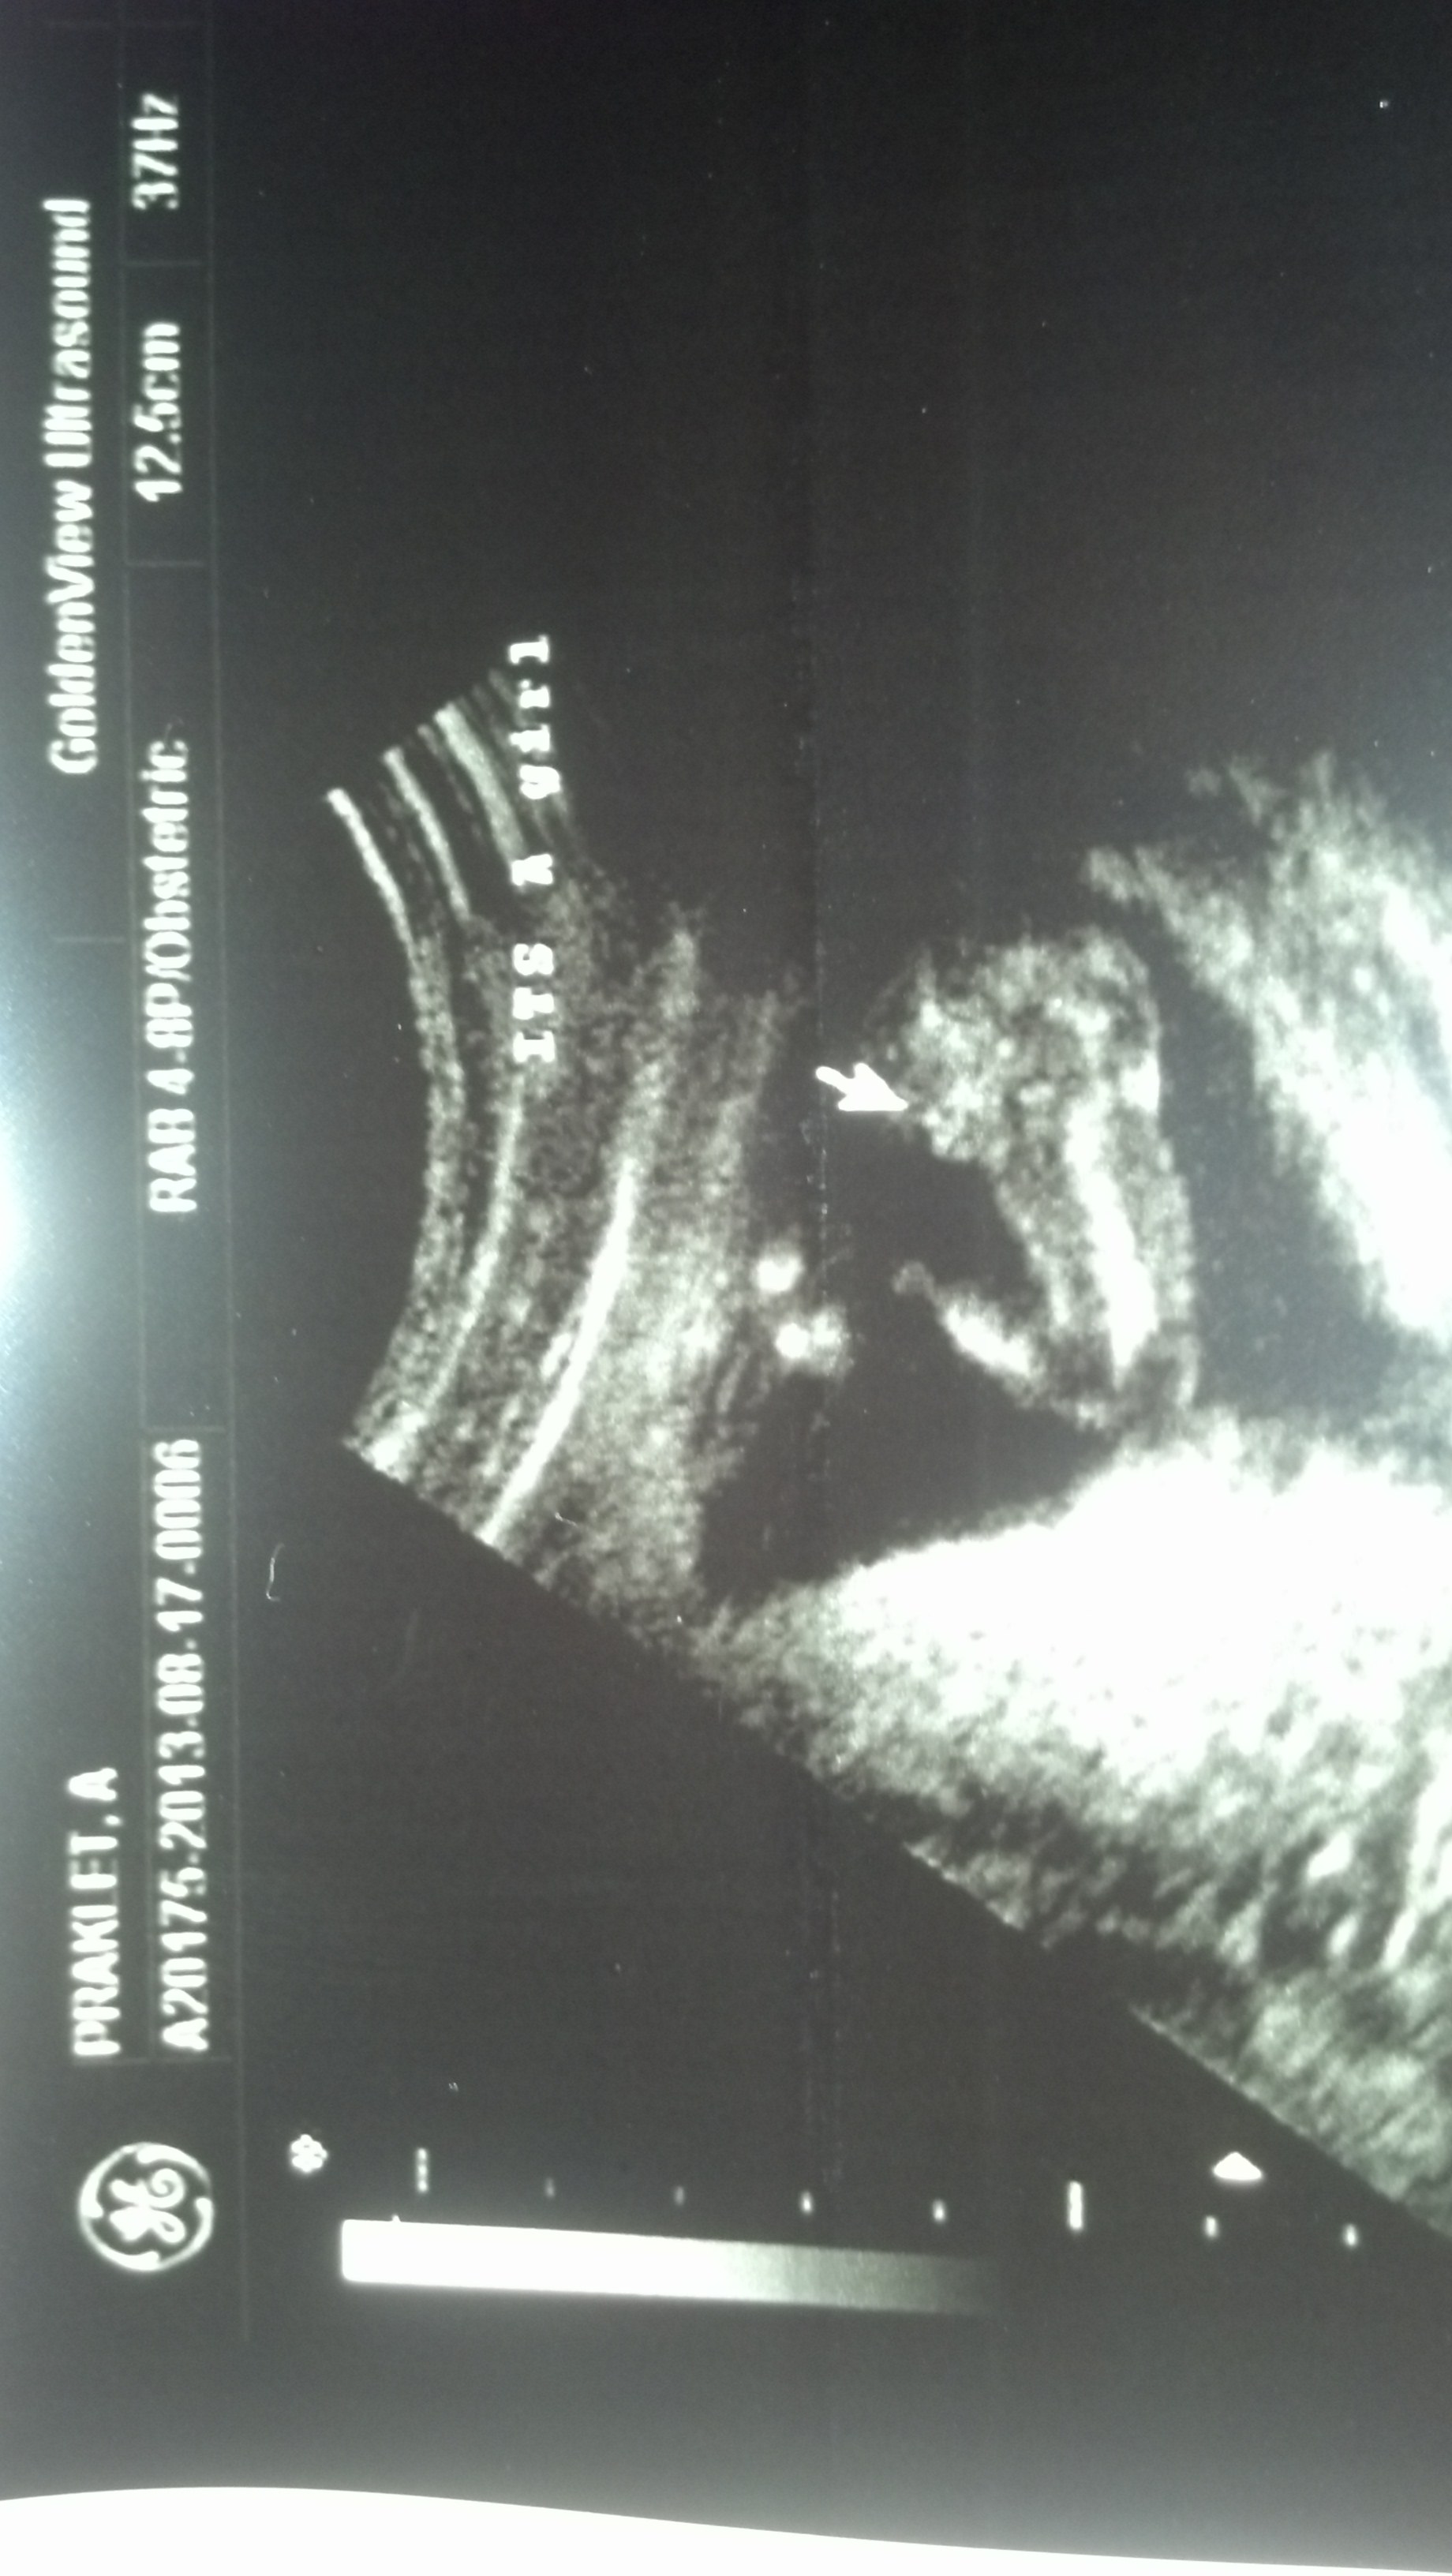

Well, I might have driven 2 hours away for a 10 min session but she checked all angles and saw three lines. SO I guess I am getting my first princess. I feel like maybe it hasnt sunk in yet cz I just feel like its a practical joke, that I couldn't be having a girl after all this time and coming up with my 2 boys. Ig I just don't really believe it yet.Attachment 13189Attachment 13190